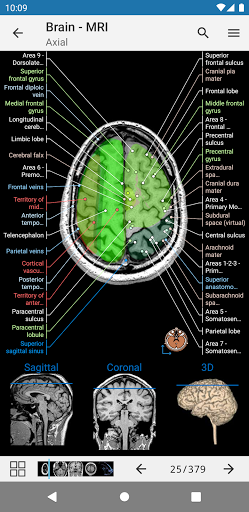

* اعثر على الأجزاء التشريحية الخاصة بك بسهولة أكبر بفضل ميزة البحث الجديدة والأكثر سهولة وقوة

* تحسين رؤية تعريفات الأجزاء التشريحية

* تصفح بين الأجزاء التشريحية باستخدام روابط الوصف